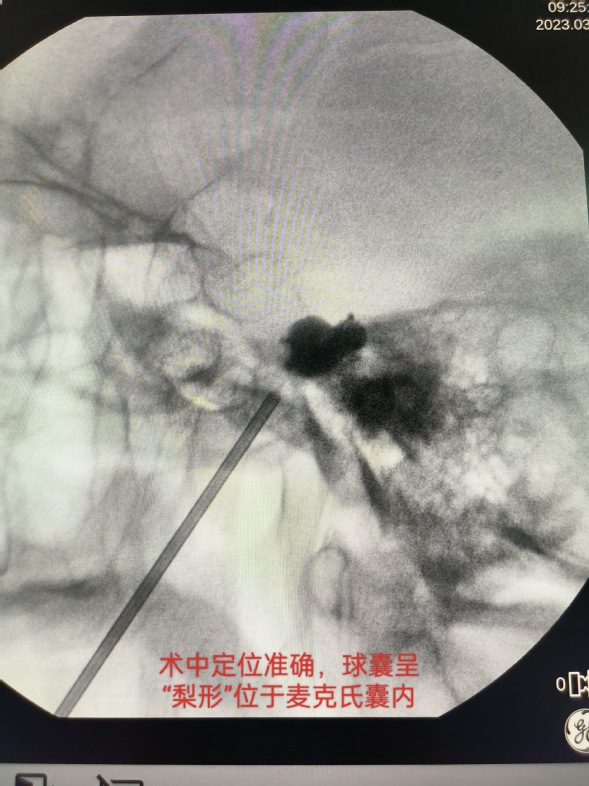

术中C型臂照相提示球囊呈梨形位于麦氏囊内,压迫2.5分钟,手术结束,总用时15分钟。